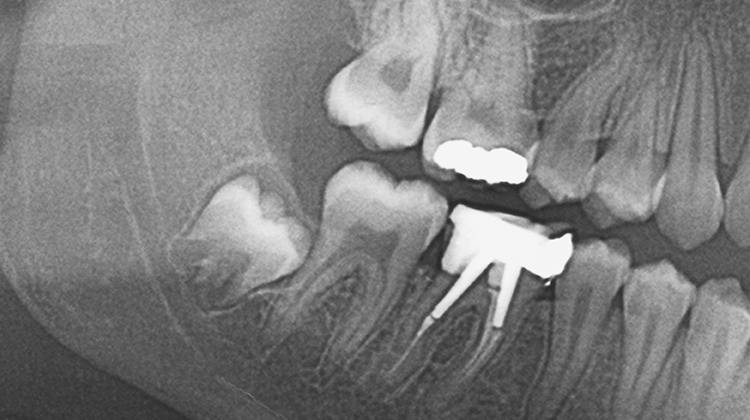

- 사랑니가 누워서 자라는 경우

- 사랑니가 누워서 자라면 바로 앞쪽 어금니 뿌리를 압박해 염증 등의 문제를 일으키거나 앞쪽 어금니와의 사이에 음식물이 잘 끼게되어 충치와 염증을 유발할 수 있습니다.